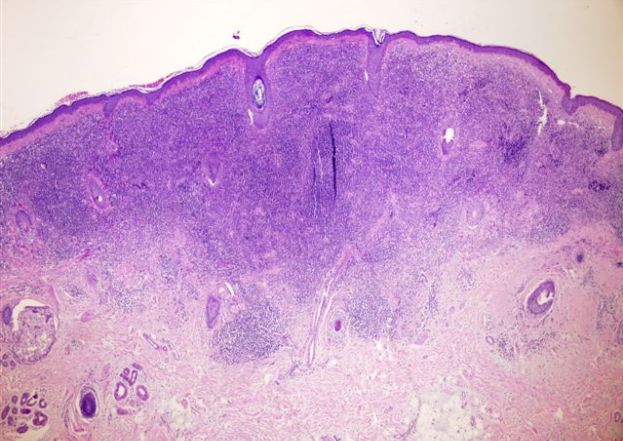

Upward elongation of the dermal papillae, giving an accentuated and sometimes irregular, undulating configuration to the dermal–epidermal junction is known as _____